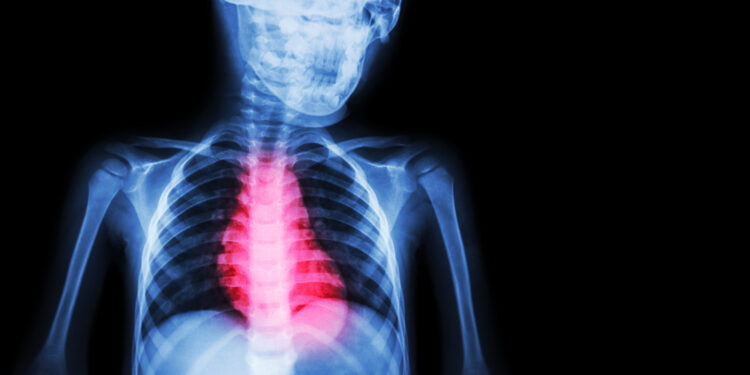

Nors simptomai dažnai primena kitus širdies smūgio tipus, NSTEMI ir STEMI skiriasi pagal tam tikrus širdies elektrinės veiklos bruožus. Vertinant širdies veiklą elektrokardiogramoje (EKG), abu infarktų tipai rodo akivaizdžių skirtumų.

- NSTEMI metu EKG galima stebėti sumažėjusią ST bangą arba pasikeitusią T bangą, tačiau Q banga neatsiranda.

- Dažniausiai šis tipas rodo tik dalinį širdies kraujagyslės užsikimšimą.

- STEMI atveju EKG matoma ST segmento pakilimas, būdingas visiškai užsikimšusiai vainikinei arterijai.

Nustatyti NSTEMI padeda kraujo tyrimai ir EKG. Tyrimai dažniausiai parodo padidėjusias širdies pažeidimą rodančias medžiagas, tokias kaip CK-MB, troponinas I ir troponinas T. Šių medžiagų lygis paprastai būna ne toks aukštas kaip kito tipo infarkto atvejais.

Galutinę diagnozę patvirtina EKG, kuri leidžia išsiaiškinti, ar iš tiesų įvyko širdies smūgis, ir nustatyti jo tipą pagal širdies elektrinio aktyvumo pokyčius.